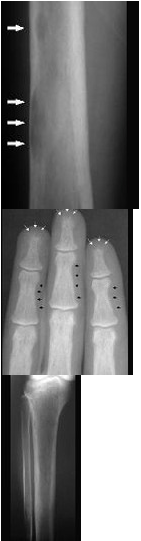

下列哪项X线表现对甲状旁腺功能亢进症有诊断价值( )

A:弥漫性脱钙

B:纤维囊性骨炎

C:骨囊肿样变化

D:骨膜下皮质吸收、颅骨斑点状脱钙

E:多发性骨折或骨骼畸形